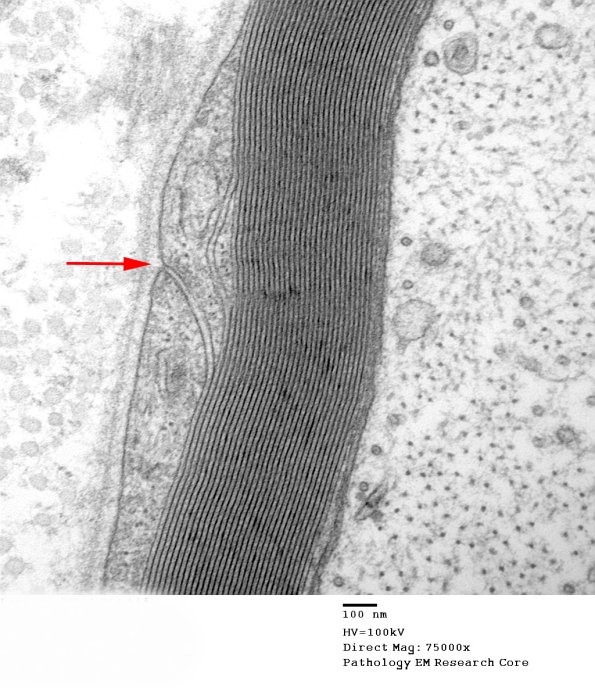

The external mesaxon, the theoretical connection of the outside extracellular space and periaxonal spaces is often marked by densities formed in adjacent elements of the Schwann cell. Also notice that the external portion of the Schwann cell exhibits a prominent basal membrane but that the inner layers forming the myelin do not. (electron micrograph)